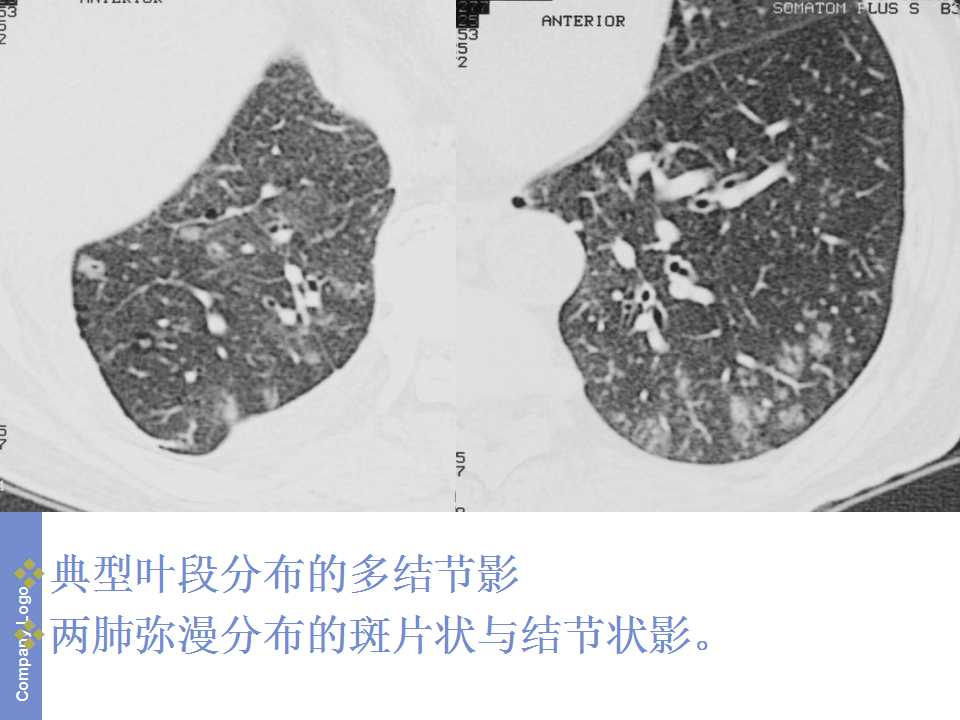

肺癌影像诊断